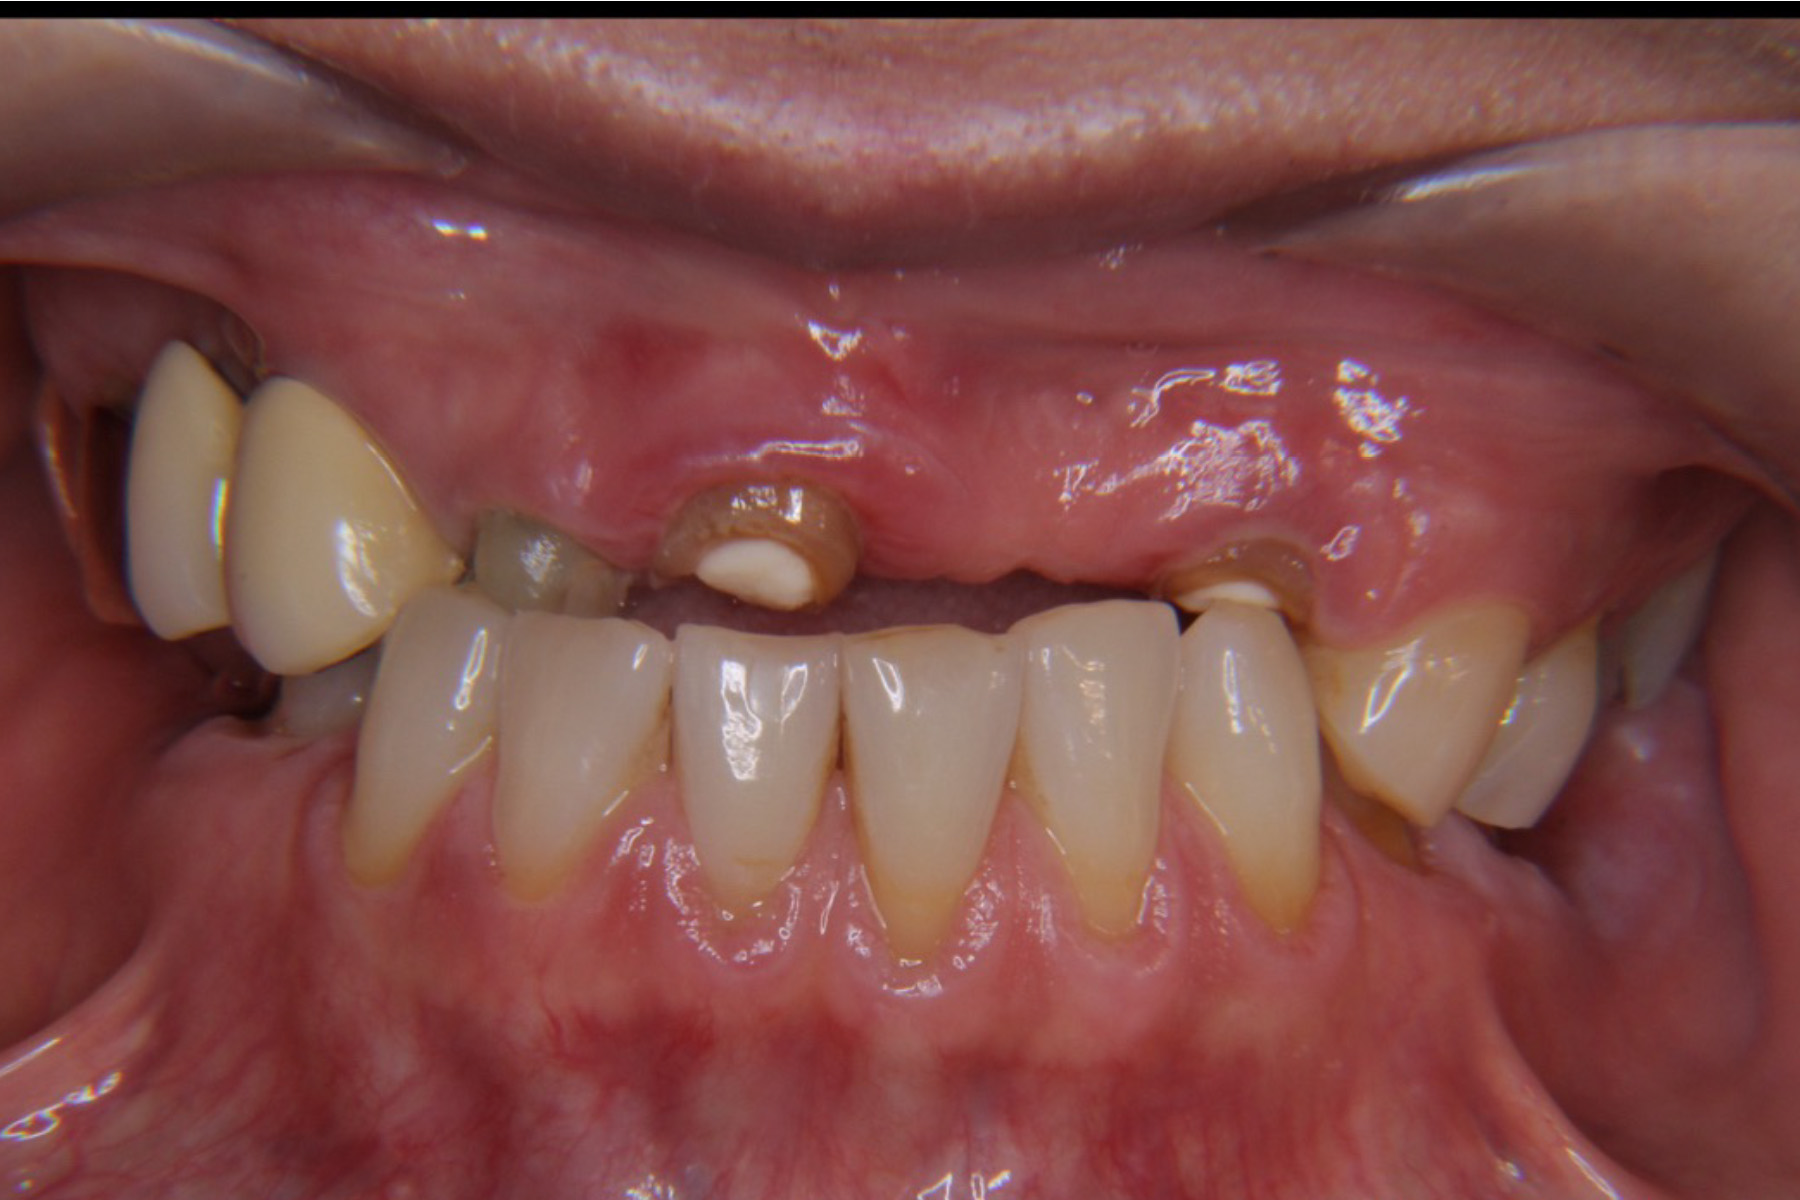

CASE16:抜歯即時インプラント

症例

CASE16